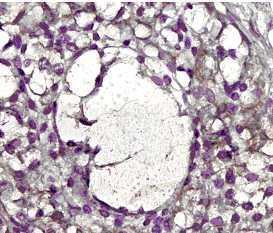

Supportive validation

- Submitted by

- GeneTex (provider)

- Main image

- Experimental details

- Detection of MMP-2 in formalin-fixed paraffin-embedded human ovary tissue using anti-MMP2 antibody (GTX30147).